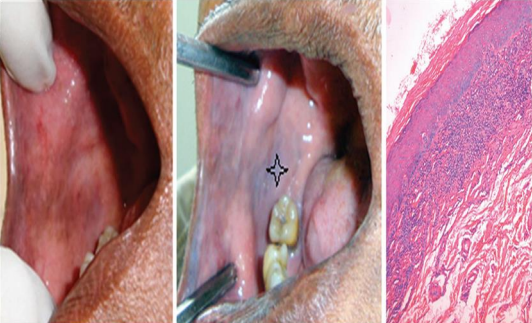

Figure 1

Figure 2

Figure 3

Figure 4